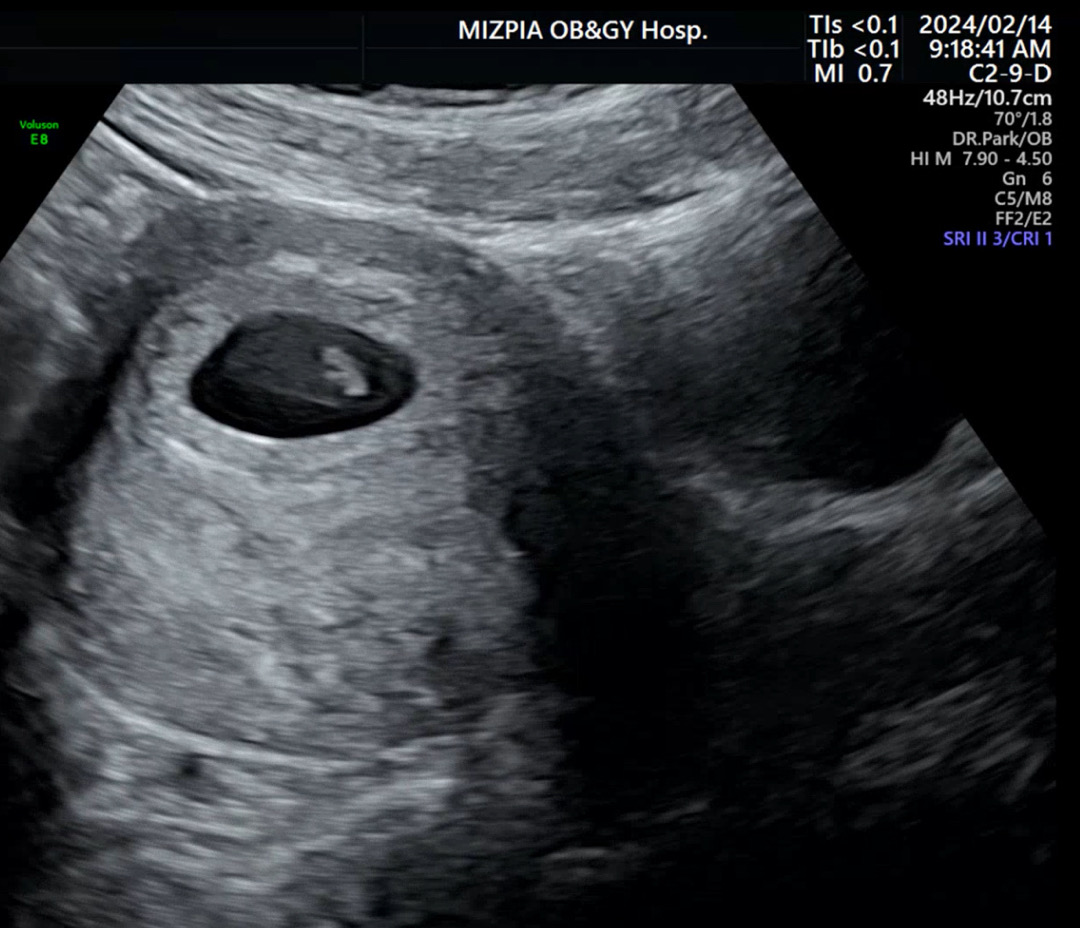

6주 3일차 첫만남! 심소 확인

오늘 처음으로 아가 만나구 왔어요! 아직 0.62cm 로 작고 소중한데 심장소리가 127bpm 무척 우렁차 마음이 벅차더라구요. 막생 기준으로는 7주인데. 아가 사이즈 기준으로는 6주 3일이라 10월 6일 출산 예정이라구 합니다. 2주전엔 아기집만 보구 와서 실감이 안났는데 이번엔 정말 실감 나네요! 아직 태명도 못 정했는데 빨리 정해서 많이 사랑해주려구요!! 🤍💙